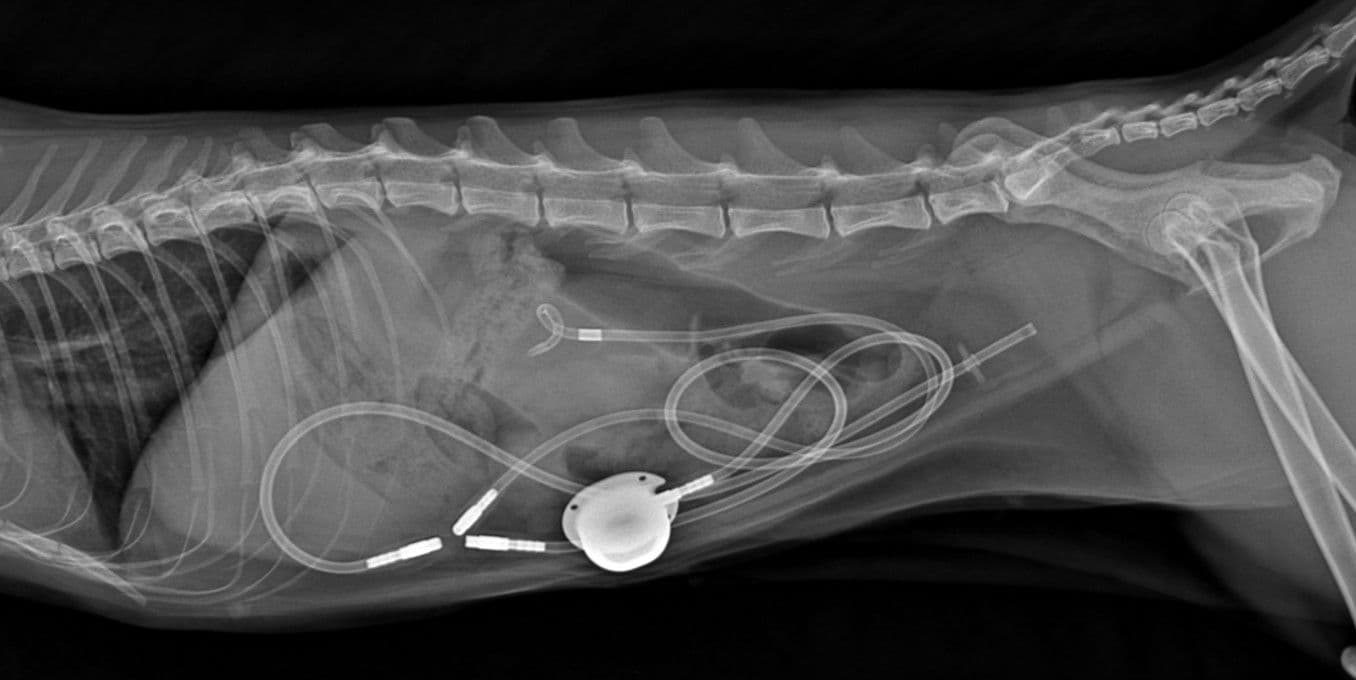

Subcutaneous Ureteral Bypass

요관 폐색을 치료하기 위한 최신 수술법으로, 막힌 요관을 대신할 우회로를 설치하여 신장 기능을 보존합니다.